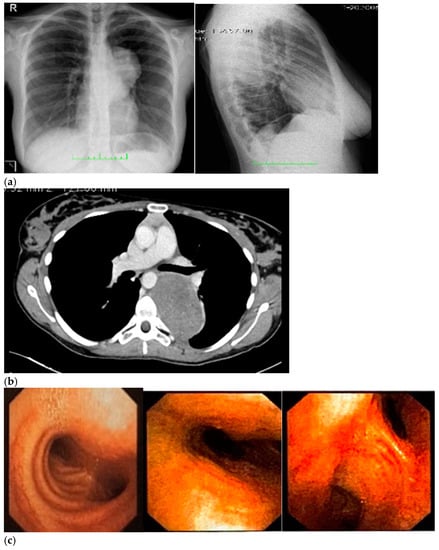

Therefore, her GP prescribed a chest X-ray, which revealed a voluminous opacity in her posterior mediastinum on the left (Figure 1a); subsequently, the GP referred the patient to a thoracic surgeon, who prescribed a series of imaging (Figure 1b–h) tests to biologically circumscribe the lesion, in order to evaluate its metabolic activity and its eventual malignancy. After these further investigations, the patient’s histopathological diagnosis was of poorly differentiated neuroblastoma ALK + (IIC), I stadium [,]. The patient was inserted in the operating room schedule for surgical excision.

Figure 1.

(a–h) Imaging assessments for pre-surgical evaluation. (a) X-ray scans. (NOTE: Voluminous opacity in the posterior mediastinum on the left, with a major axis of about 12 cm). (b) Thorax CT scan with Iodixanol. (NOTE: Solid, oval-shaped tumour in the left posterior mediastinum, measuring 8 × 5.5 cm. Anteriorly, the mass pressed the left main bronchus from behind, while medially it displaced the thoracic aorta—sitting directly on the metamers T5 to T8, and compressing the hemiazygos vein. The mass also went through the intervertebral foramen, between T6 and T7, and partially through the VI and VII intercostal spaces; laterally, it caused dystelectasis of the lung parenchyma. The NB had an irregular density, with innumerable small foci of calcification, and areas of slightly blurred impregnation of the contrast medium). (c) Tracheobronchoscopy. (NOTE: Left lower lobe bronchus with a luminal narrowing, resembling an extrinsic compression. In detail: left lower lobe bronchus, left main bronchus, trachea and carina). (d) Thorax MRI with Gadoteridol. (NOTE: Presence of a mass with maximum dimensions of approximately 7.5 × 5.5 cm axially and 10 cm of craniocaudal extension, limited by a plane passing from upper T6 to lower T9. Extension up to the ipsilateral lung, which caused a moderate compression and a slight compressive effect, also on the left sections of the heart (in particular the atrium). Slight anterior displacement of the ipsilateral pulmonary hilum structures; the neoplasm also came into contact with the aorta. The tumour went through the left T6–T7 intervertebral foramen—taking up space at the foraminal level, not at the level of the spinal canal—and it also extended up the corresponding intercostal space; it was compatible with a lesion originating from the nerve sheath arising from the T6–T7 foraminal region). (e) Total-Body PET/CT. (NOTE: Presence of an increased glucose metabolism lesion in the posterior mediastinal area, showing a necrotic portion and a metabolically more active portion, located in the medial side and infiltrating the posterior arch of the 6th left rib). (f) Thorax CT scan with Lopromide. (NOTE: Minor volumetric increase of the known space-occupying lesion, which maintained similar densitometric characteristics, clear limits, and maximum diameters equal to 8.5 × 6 cm on the transverse plane, with a maximum longitudinal extension of 11 cm. The solid component which went through the intercostal space between T6 and T7 was substantially unchanged. Absence of pleural or pericardial effusion). (g) Total-body scintigraphy with metaiodobenzylguanidine. (NOTE: The examination confirmed that the neoplasm was confined to the mediastinum only. The area of greater contrast medium enhancement corresponded to the left hemithorax, in particular, to the left posterior mediastinal region, from T6 to T9). (h) Thorax MRI with Gadoteridol. (NOTE: Slight increase in size of the known space-occupying lesion in the posterior mediastinum (85 × 60 × 103 mm vs. 80 × 55 × 100 mm). At T6–T7 level, the mass occupied some left foraminal canal space. Next to the known lesion, pleural effusion thin layer (maximum thickness of 11 mm)).